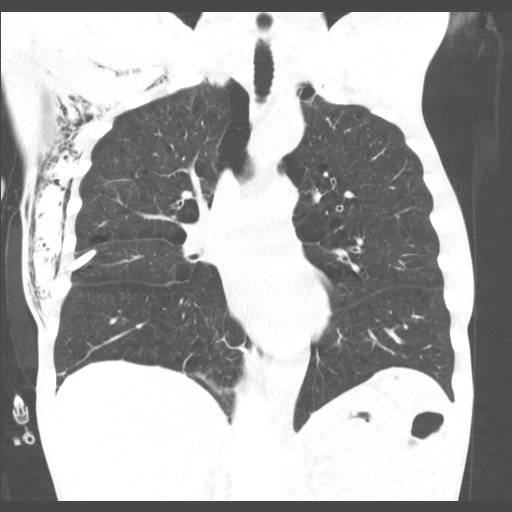

Re-expansion pulm. edema: rare important cause unilateral edema after (wait for it) rapid lung expansion after thoracentesis or PTX. Mortality up to 20%, prevent by removing < 1.5 L fluid. Complete recovery after < 1 week in this case. #chestraded #FOAMrad #FOAMed